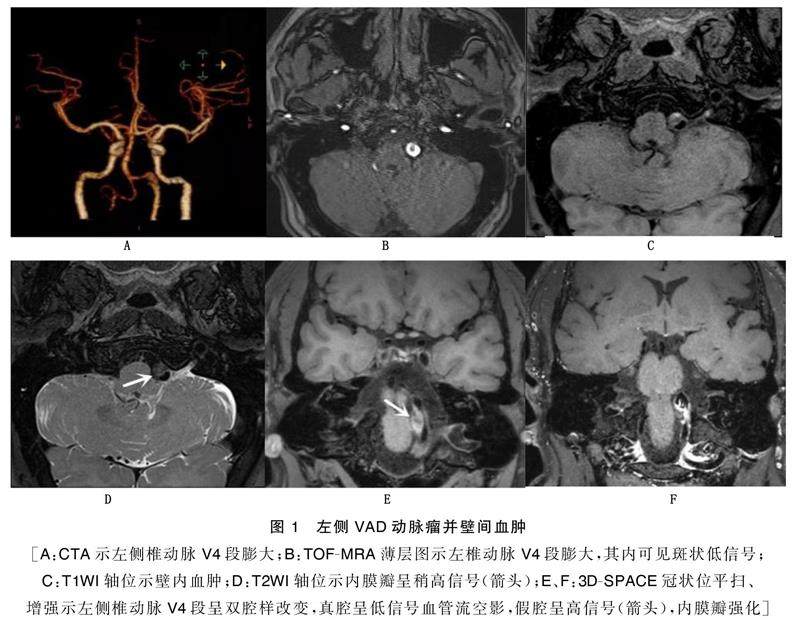

摘要目的:探讨高分辨率磁共振血管壁成像(HRMR-VWI)在椎动脉夹层诊断中的应用价值。方法:搜集2例经临床证实为椎动脉夹层病人的临床及影像资料,均获取磁共振时间飞跃法磁共振血管成像(TOF-MRA)、快速自旋回波T1加权成像(T1WI)、快速自旋回波T2加权成像(T2WI)、三维可变反转角快速自旋回波(3D-SPACE)、T1WI常规剂量增强扫描(CE-T1WI)成像,分析椎动脉夹层的临床特点及影像特征。(剩余6375字)

高分辨率磁共振血管壁成像对椎动脉夹层的诊断价值